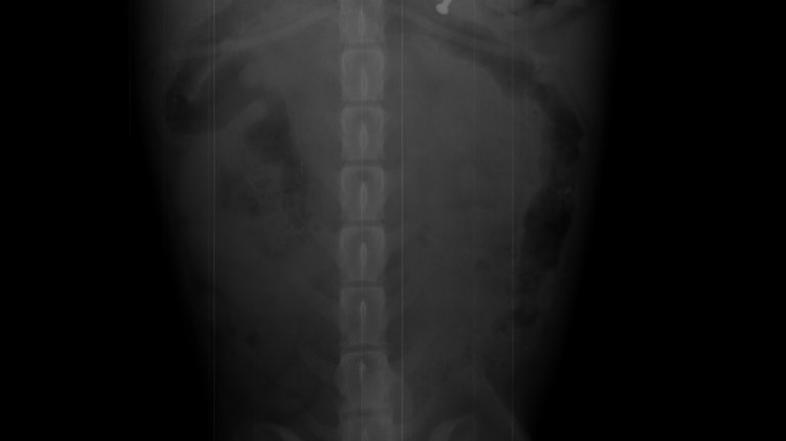

Tjaša Kokalj se je pred kratkim močno ustrašila za zdravje svojega štirinožnega prijateljčka, psička Kukija. Kosmati lepotec je namreč pojedel žebelj, ki ga ni mogel izločiti po naravni poti, zato so ga morali veterinarji naslednji dan operirati. "Videla sem, kako je Kuki pojedel žebelj, ki je padel na tla. Če tega ne bi videla, sploh ne bi vedela, da je z njim nekaj narobe. Ves čas se je namreč obnašal povsem normalno," nam je izdala Tjaša, ki je s kužkom takoj pohitela k veterinarju. "Rada bi se zahvalila ekipi Medicoveta za hitro in prijazno odzivnost,“ nam je še povedala Tjaša in priznala, da bi bila še bolj panična, če ob njej ne bi bilo fanta in tako prijaznih veterinarjev.

Izvedeli smo še, da se Kuki, ki ima osem šivov, po operaciji počuti že veliko bolje.